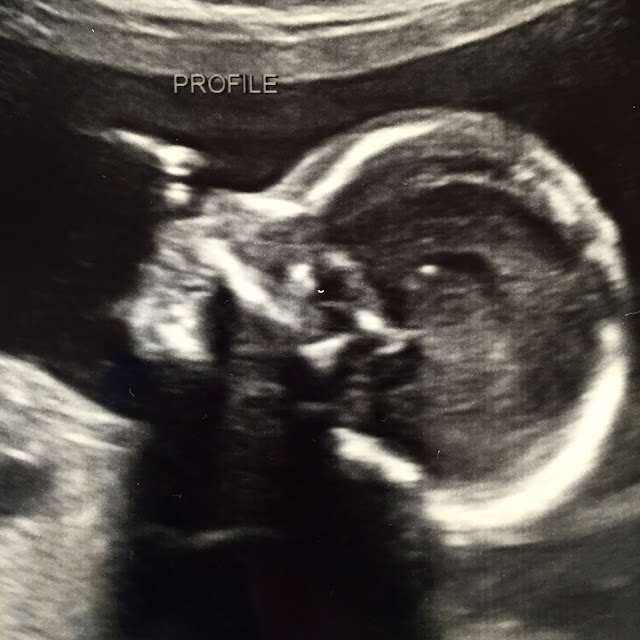

While our kids were at the party I had another ultrasound followed by another appointment with my doctor to check on the baby. Despite the never-ending nausea our little girl is healthy and well!

Feb 14th: I'm so very grateful for all the extra prayers, they are making such a difference! I was blessed with another little peek at our baby girl today... She is doing well and my placenta has also moved up a few centimeters over the last two weeks to just above the low-lying/problem area! My next appointment isn't for a month! Deo gratias! #21andahalfweekspregnant

As of tomorrow, Feb 25th, our baby girl will be 23 weeks!